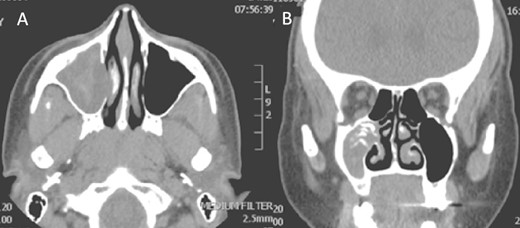

A 12-year-old young girl with relapsing acute myeloid leukemia presented with fever, headache, and left maxillary facial pain. Her symptoms were associated with blood-tinged nasal discharge. Nasal endoscopic examination showed friable ulcerative mucosa of the left middle turbinate and osteo-meatal complex which raised a clinical suspicion of invasive fungal sinusitis. Thus, a contrast-enhanced CT scan (CECT) (Fig. 3) was necessary which showed enhancing left maxillary sinus opacity suggestive of acute invasive fungal sinusitis. The patient underwent urgent endoscopic medial maxillectomy with removal of invasive fungal debris (Fig. 4) along with debridement of left middle turbinate, medial maxillary wall, and orbital floor. A diagnosis of invasive mucormycosis was confirmed by histopathology. The patient was started on aggressive treatment in the form of intravenous and oral antifungal medications. She was regularly followed up for the next 5 years with no evidence of recurrence.

Coronal (A) and axial (B) CECT scan images showing left complete maxillary sinus heterogenous opacification.